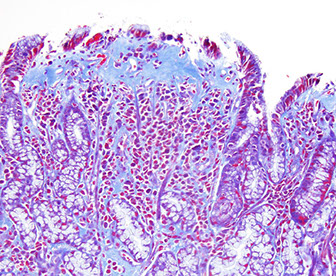

Collagenous gastritis

Collagenous gastritis - trichrome [1]